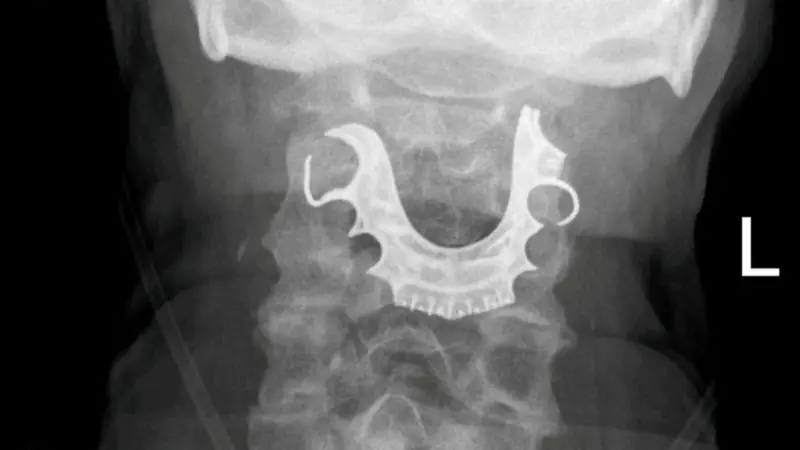

La dentadura postiza de un hombre de 72 años se encontró alojada en su garganta ocho días después de la cirugía, lo que provocó complicaciones y lo obligó a someterse posteriormente a un procedimiento de emergencia.

El hombre, un electricista retirado, se sometió a una "operación menor" para extraer un bulto benigno en su estómago cuando sus dentaduras postizas, una placa de techo de metal con tres dientes postizos, se desprendieron, informó SWNS, citando informes de casos de BMJ. SWNS no dijo de dónde es el hombre o dónde se realizó la cirugía.

Pero no mejoró y fue ingresado en el hospital solo dos días después. Los médicos le dijeron a los médicos que "vieron un objeto semicircular sobre sus cuerdas vocales", según SWNS.

Luego, el hombre se sometió a una cirugía de emergencia para extraer la dentadura postiza de su garganta. Pasó seis días en el hospital antes de ser dado de alta, solo para regresar nuevamente debido a la pérdida excesiva de sangre.